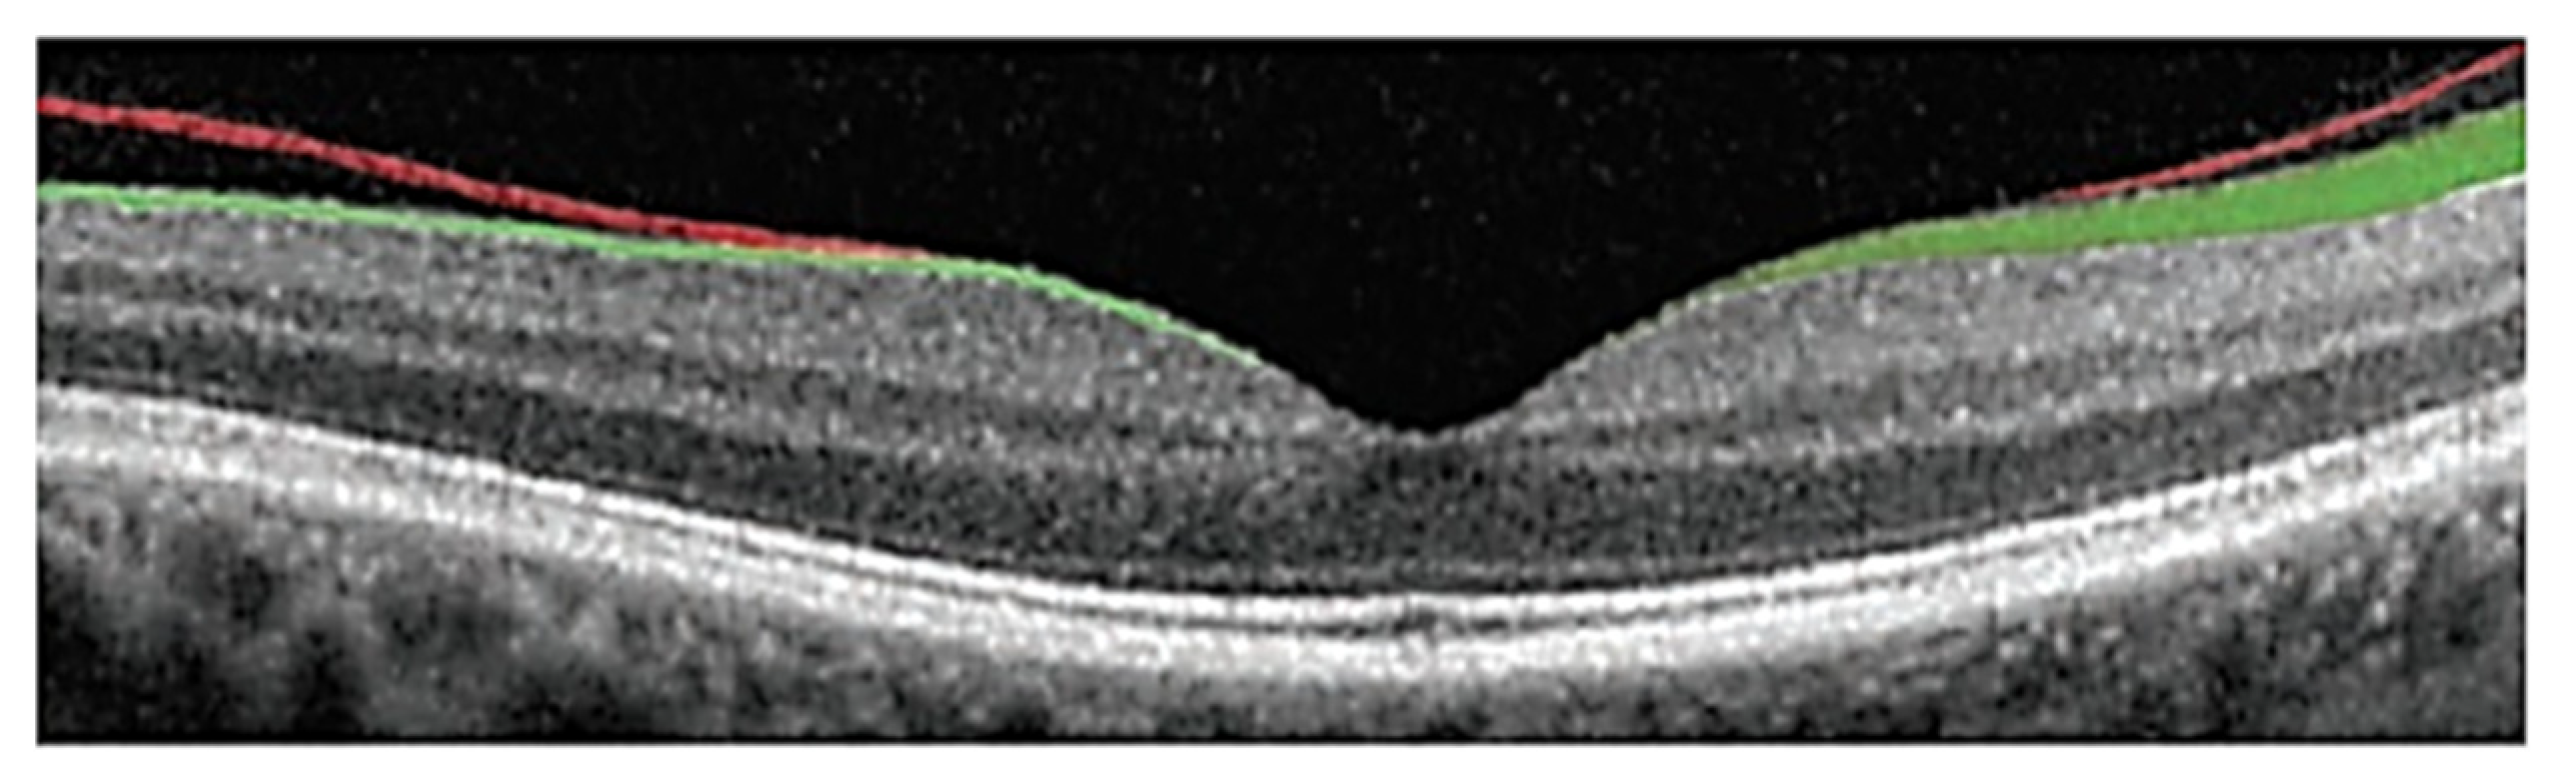

4.2. Segmentation of Subretinal Layers of OCT Images